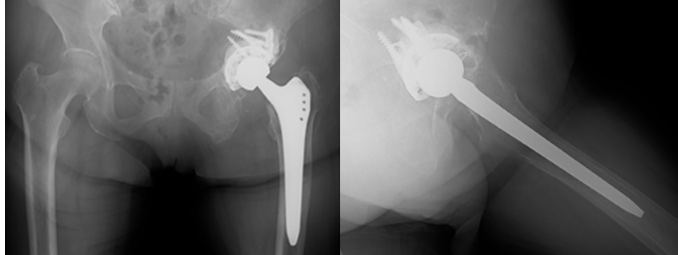

Surgery was completed without complications. Pain relief was immediate, and gait training began the day after surgery. By post-operative week 2, the patient achieved independent ambulation. Denosumab was recommended, but the patient and her family disagreed with the administration. At 6 months postoperatively, she developed numbness and weakness in the left leg. CT showed extensive metastatic involvement of the left sacrum and ilium (Fig. 6).

Figure 6: Computed tomography at 6 months postoperatively showing extensive metastatic involvement of the left sacrum and ilium (arrowheads).

Although acetabular osteolysis progressed and medial migration of the implant was observed (Fig. 7), construct stability was preserved, presumably due to the wide surface area of the GAP II ring.

Figure 7: Radiograph at 6 months postoperatively showing medial migration of the acetabular cup and progressive osteolysis, while construct stability is preserved by the wide contact surface of the reinforcement ring.